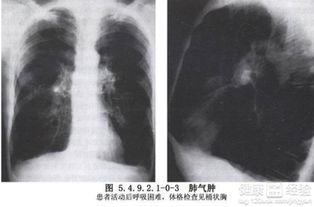

肺氣腫早期常無癥狀或僅感到氣促、胸悶、呼氣不暢。隨病情發(fā)展會感到進行性呼吸困難,上樓時氣喘吁吁,心慌氣促,胸部呈圓桶狀。由于肺通氣和換氣功能障礙,常可造成缺氧、口唇、指甲有紫紺,可形成槌狀指,在寒冷季節(jié),特別是抵抗力和肺功能較差的老年病人,易合并肺部急性感染,加重病情,可發(fā)生呼吸衰竭。

肺氣腫是指終末細支氣管遠端(呼吸細支氣管、肺泡管、肺泡囊和肺泡)的氣道彈性減退,過度膨脹、充氣和肺容積增大或同時伴有氣道壁破壞的病理狀態(tài)。按其發(fā)病原因肺氣腫有如下幾種類型:老年性肺氣腫,代償性肺氣腫,間質(zhì)性肺氣腫,灶性肺氣腫,旁間隔性肺氣腫,阻塞性肺氣腫。